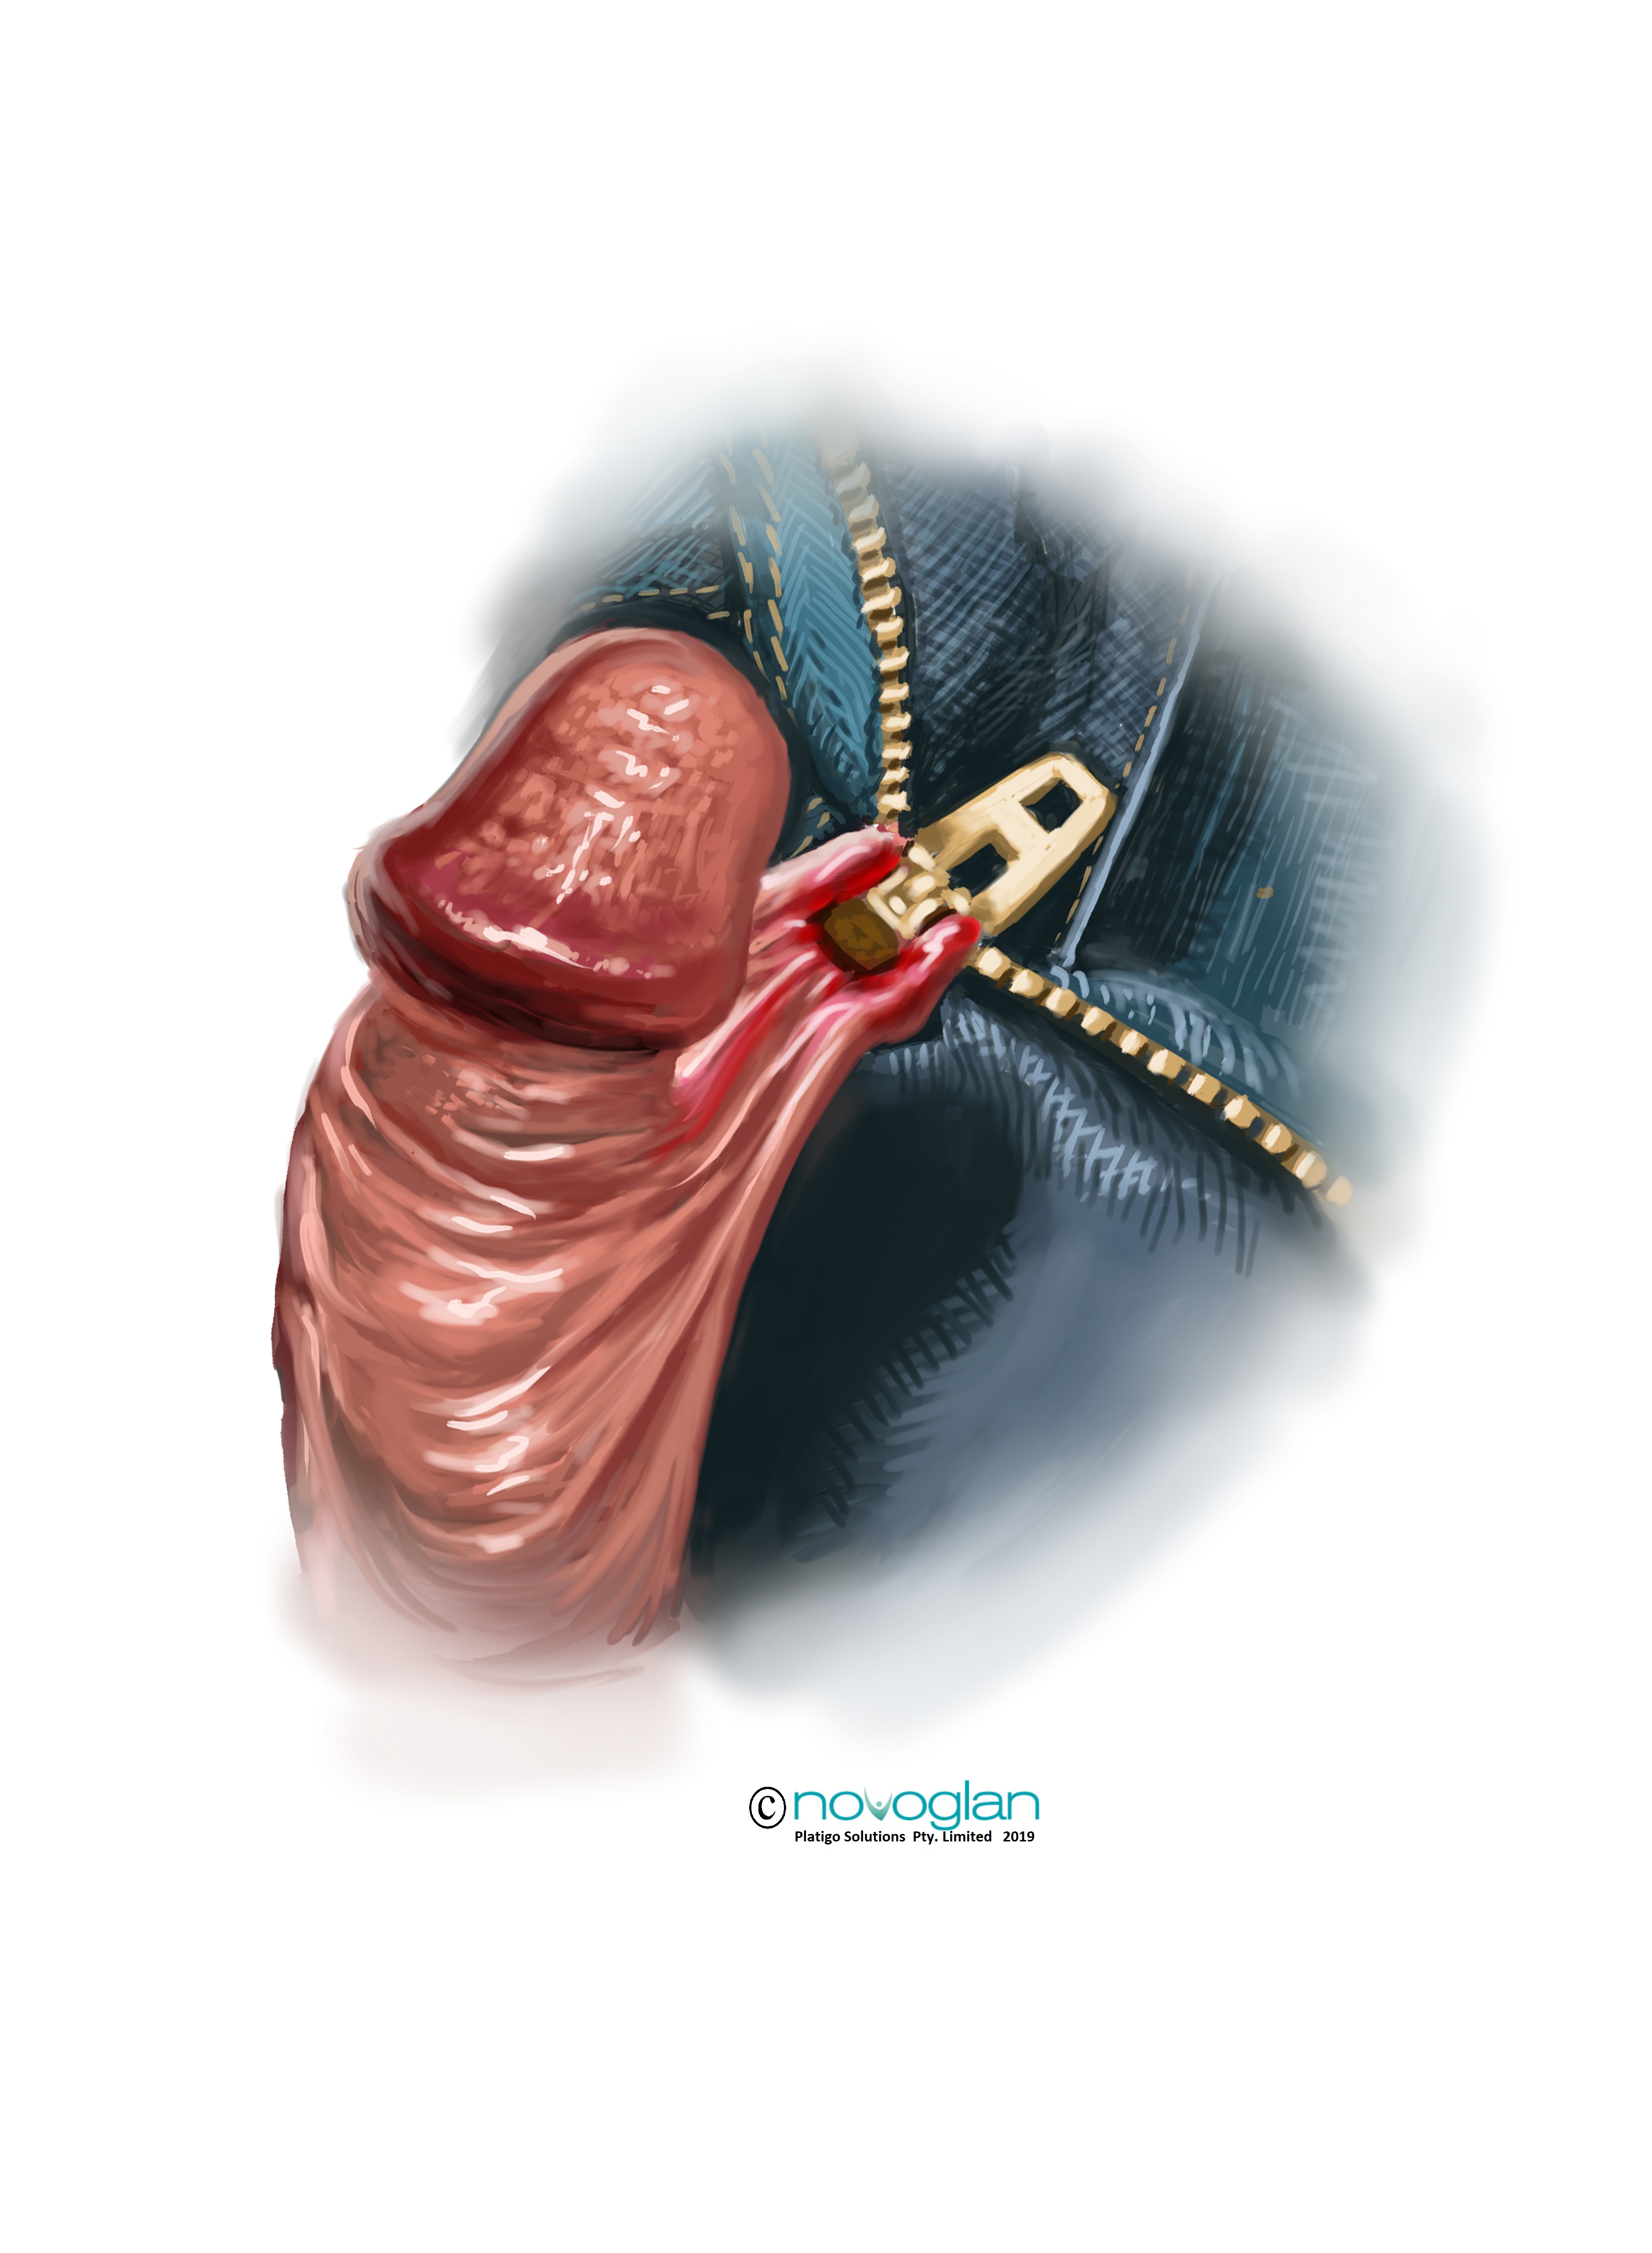

5: Tears, Cracks & Zipper Trauma of the Foreskin.

Tears, Cracks & Zipper Trauma of the Foreskin

From time to time the foreskin can become torn, cracked or traumatised. The phenomena of the zipper trauma has been identified in the medical case literature as being a phenomena that occurs when a man does not pay due attention to the closing of the zipper on a pair of pants. The foreskin usually gets caught, often through the undergarments, and is dragged into the space in between the teeth of the zipper and this causes significant trauma. In some severe cases this has resulted in full amputation of the foreskin. Generally the tissue is treated with a local anaesthetic and then released or cut from the zipper and where appropriate, stitches or more modern skin closing techniques are used to seal the wound. It is not uncommon for scar tissue to form at the site of the injury. The use of foreskin cream or other dermatologically recognised anti-scarring formulations may be of help in trying to reduce the formation of a scar.